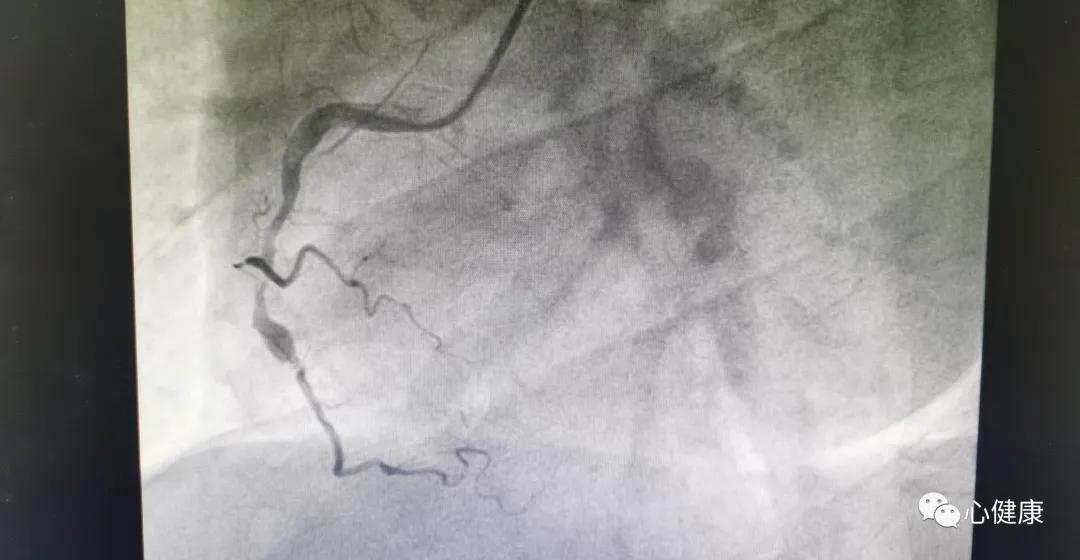

32岁时心梗一次,到41岁的时候再次发生心梗!这样的情况即便是在现实世界中,也是很少出现的!但在陈医生的病人中,就真实的发生了!

其实很简单,就是冠心病家族史!也就是我们常说的冠心病基因!患者父母都有冠心病,这或许才是患者年纪轻轻罹患两次冠心病的主要原因!